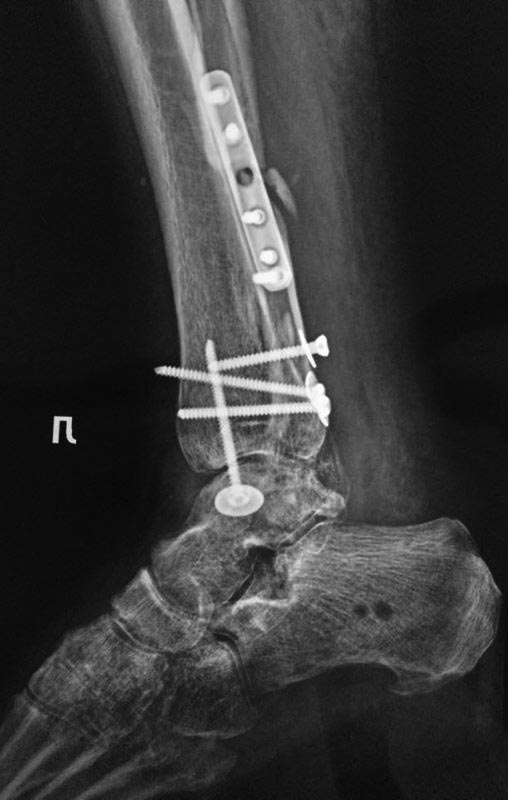

После остеосинтеза лодыжек

А вот такую задачку нам задали друзья с севера. Операция в мае этого года. На данный момент пациент опереться на конечность не может.

Возраст: за 50. Движений в голеностопном суставе практически нет ( в пределах 10-15 градусов) суставы стопы функционируют. Умеренная контрактура. Ходит с костылями, приступает на ногу. Нагрузка не по оси. Внешний вид: застарелый отек.Да, и забыл отметить. Обратите внимание на синтез заднего края. Доступ с отсечением ахилла

Если это свежие рентгенограммы, то у больного имеется несращение перелома медиальной лодыжки, неустраненное повреждение синдесмоза ---> нестабильность ---> неопорная конечность. Показан реостеосинтез медиальной лодыжки и, восстановление синдесмоза стягивающим (не позиционным, как в свежим случаях) винтом 4 кортикала в нейтральном положении стопы. Ранняя нагрузка в брейсе или без. Не споря о точной терминологии (КРБС, нейродистрофеский с-м и т.д.), следует максимально быстро восстановить опороспособность конечности. Для этой стопы осевая нагрузка важнее подвижности в суставе.

Руки необходимо поотбивать тому, кто делал остеосинтез. Подвывих стопы, несращение внутренней лодыжки, остеопороз. Разве этого мало?

Скорее всего репозиция медиальной лодыжки не достигнута из=за укорочения малоберцовой кости. Любая операция в этом состоянии трофики лишь усилит боль и пороз, не позволит добиться функционального результата. Согласен с коллегами, которые предлагают нагружать ногу в ортезе. Возможно подключить бисфосфанаты, большие дозы Дз и ударно-волновую терапию. Последнее я практикую уже 9 лет , отмечается быстрая редукция боли и отека. Через пару месяцев я бы удалил винт из медиальной лодыжки и не пытался бы ее фиксировать,а косой остеотомией удлинил бы малоберцовую, что позволит исправить латерализацию таранной кости. В дальнейшем ходьба с супинаторами , время определит сроки артродеза.